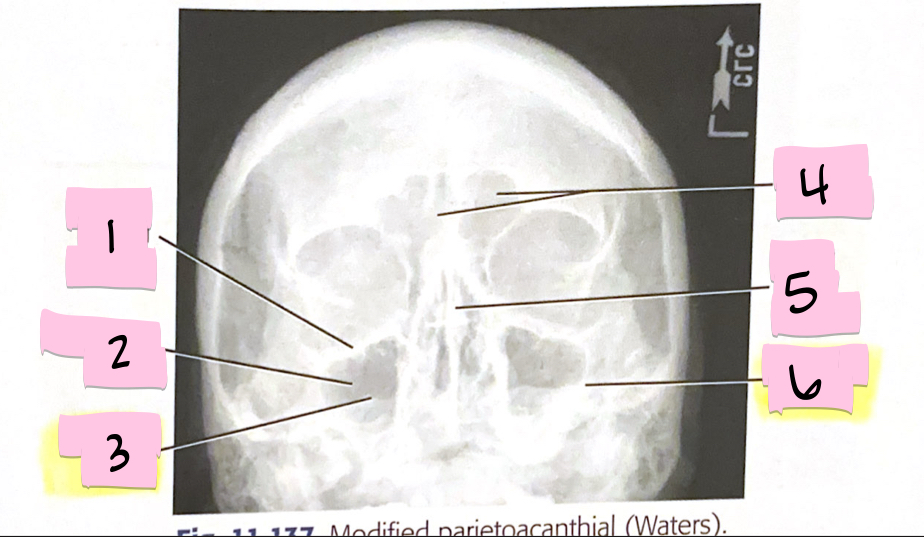

What is 1 pointing to?

Inferior orbital margin

What is 2 pointing to?

Maxillary sinus

What is 3 pointing to?

Petrous ridge

What is 4 pointing to?

Frontal sinuses

What is 5 pointing to?

Bony nasal septum

What is 6 pointing to?

Petrous ridge